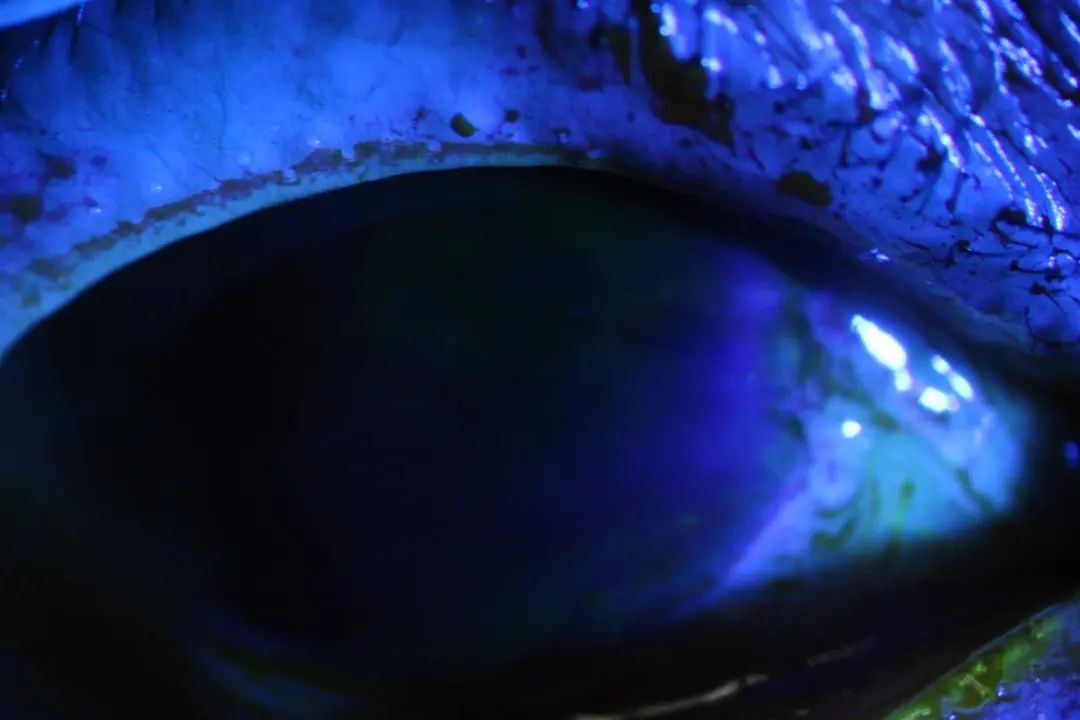

就诊后左、右眼检查结果

为了防止化学成分残留,夏朝霞交代护士翻开王阿姨眼睑,予大量生理盐水冲洗,随后予眼膏包眼,并滴用成纤维生长因子滴眼液,促进王姨角膜上皮修复。